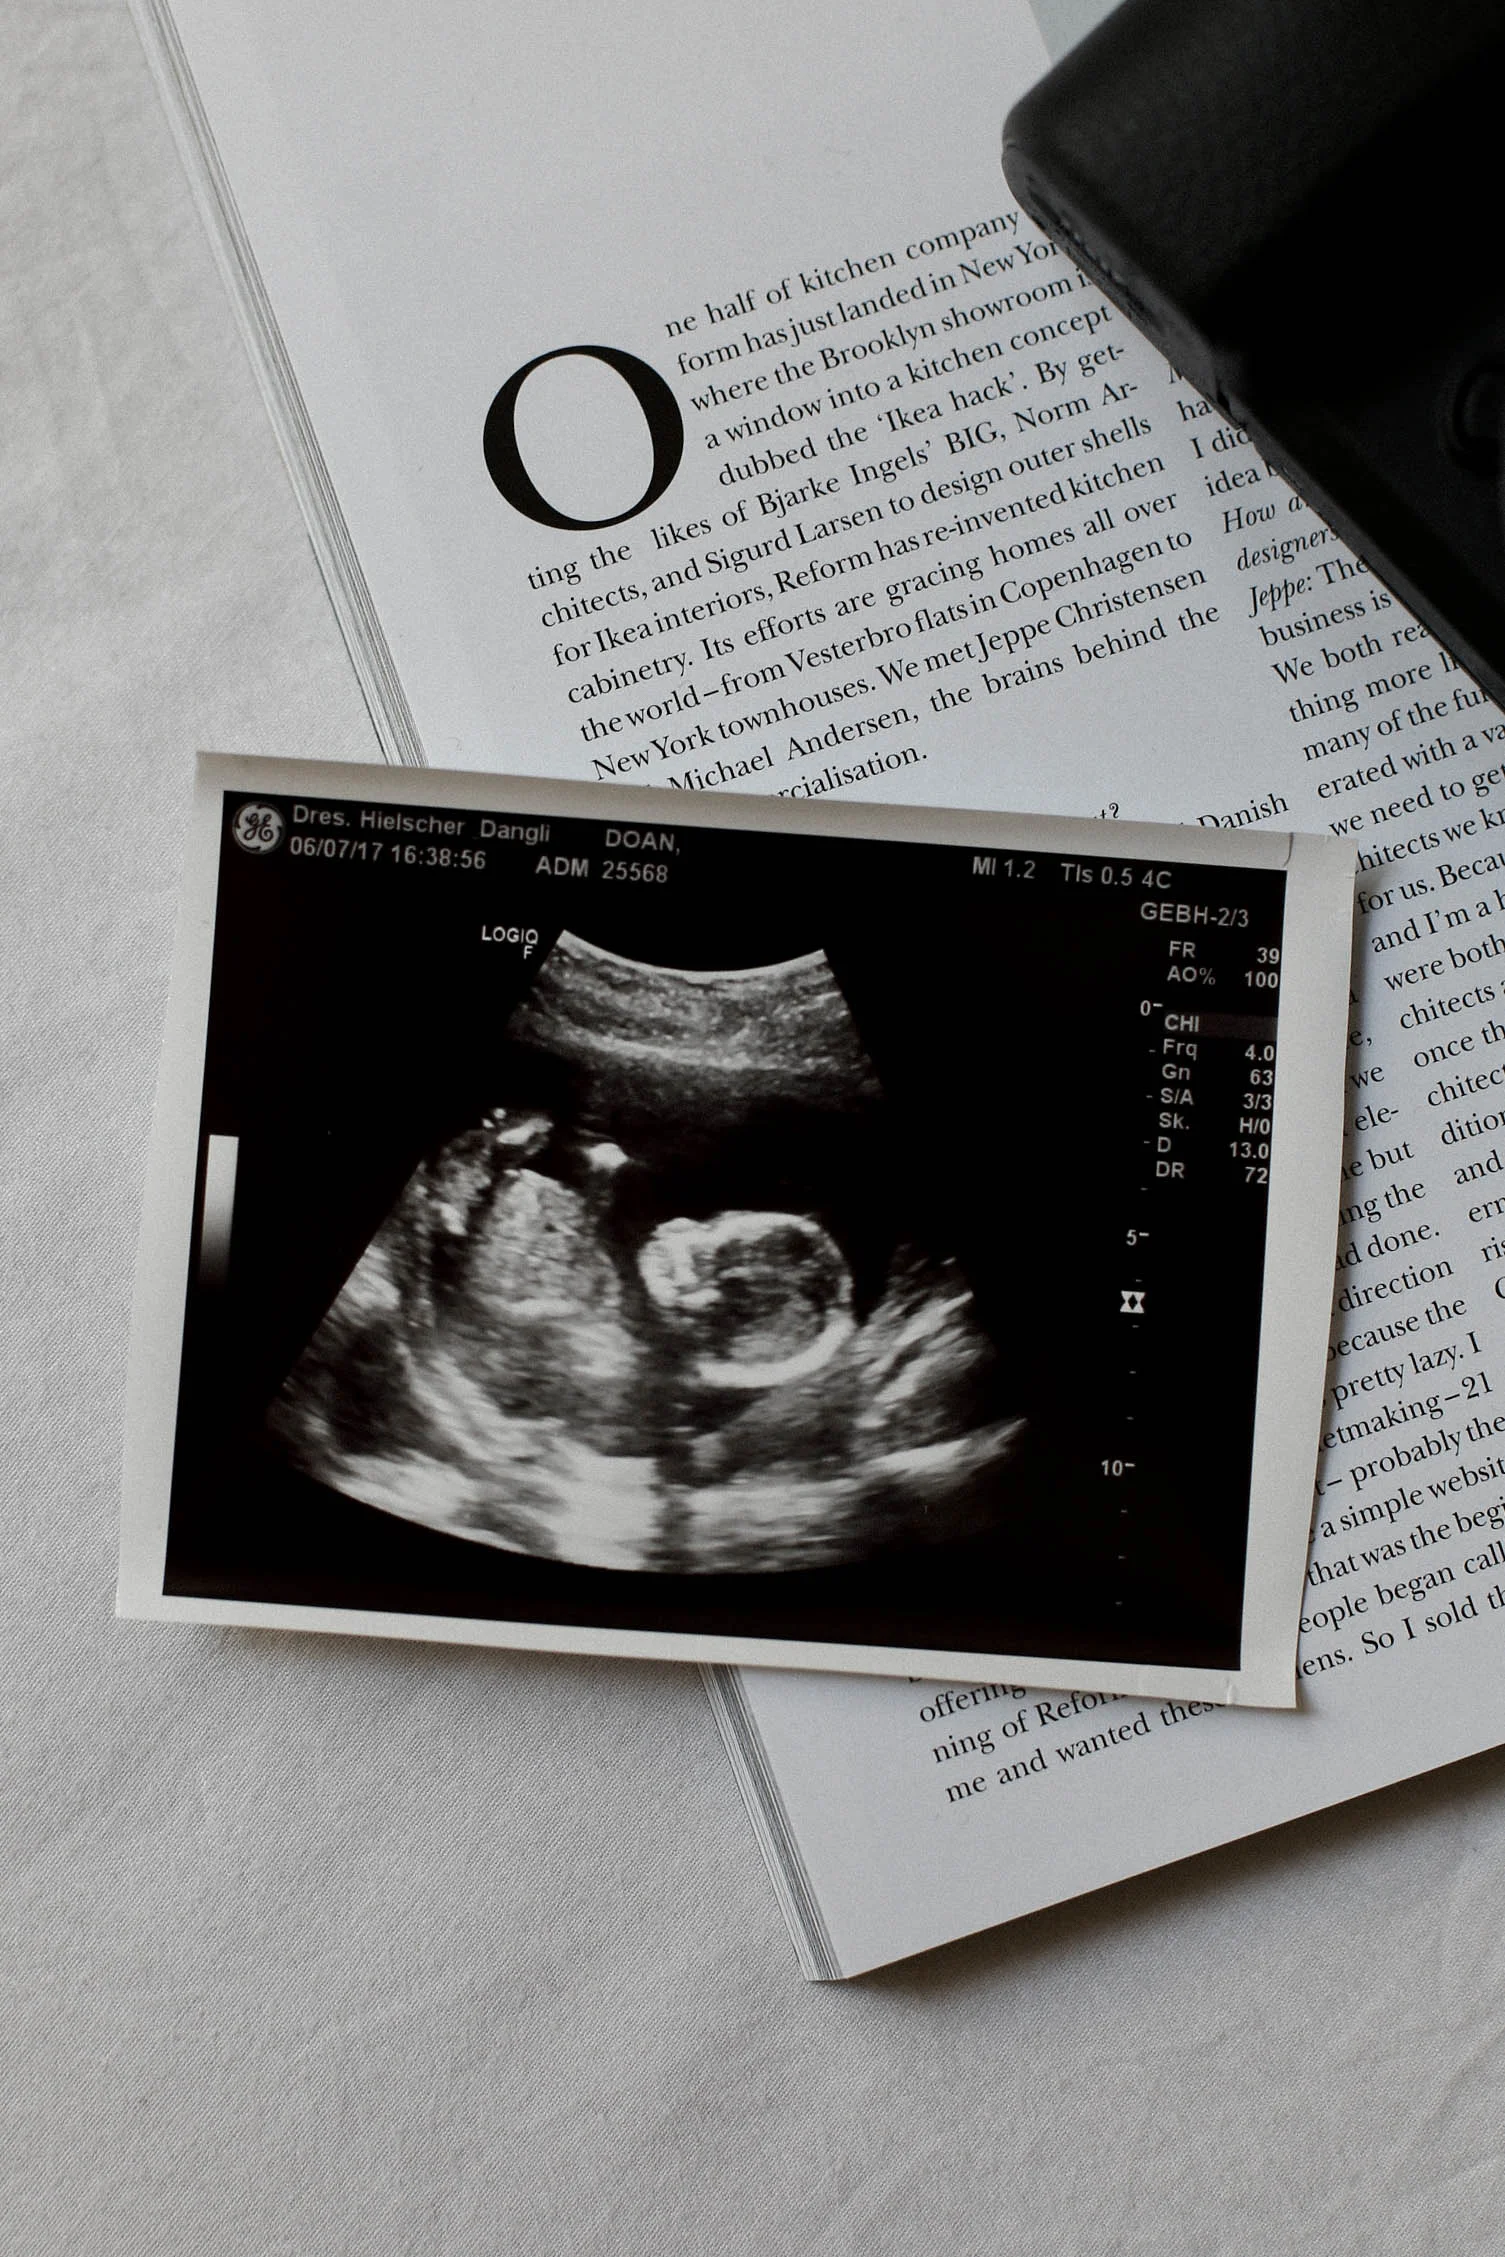

BERLIN DAY 3: I saw Julia Junior's heartbeat and toes !!

And it was a good decision.

I don't know whether it was just the hospital I went to for my first check up (Benh Vien Phu San Quoc Te on Bui Thi Xuan Street), or those specific doctors, but I felt treated like I came in for a running nose and not to confirm that I'm expecting my first child ever. It was super unfriendly and just not what I would expect from doctors who deal with people who are about to become mom's. In Germany announcing a pregnancy is still a big awwwww and congratulations thing. At that hospital I was treated like, you are 7.5 weeks pregnant, here is your ultrasound photo, go get the blood test, come back in two months. No explanations, nothing. And I paid like 200$ for everything. They also gave me medicine with no explanations, I googled them and decided not to take them. I don't trust medicine that has no google record except for random Vietnamese websites and the Korean pharmacy company website. So yeah, I went for my second check up here in Berlin at my gynaecologist and he was super kind and friendly, explained a billion things to me, told me what to take care of, what not, and it was just a much more pleasant experience. I might change to benh vien hanh phuc after I come back to Vietnam and if I don't like it there either I'll definitely do all my check ups in Germany and probably give birth in Germany. Let's see. Anyway, ultrasound !!! I was super worried about my baby because I've been having stomach pain and everything. I'm a pessimist, what if it died in my belly and i didn't know (ok too extreme lol). But what if ??? So I didn't even accept the fact that I will be a mother until I saw its heart beating on that ultrasound screen and when I saw the arms and legs and all the five toes, I was close to tears. What an experienceeeeee. Seriously. There's something inside of me man : )))) You know I'm not the girly girly girl who is like super optimistic, warm and always happy. I'm more a pessimist and prepared for the worst, but I am looking forward to Julia Juniorrrr. The only thing I'm worried about is stretch marks (no after long research, cremes barely help), and my bigger getting boobs. And breastfeeding and teared up nipples and all that. Sounds horrible to me. But I trust all the millions of women who have done this before me and say that everything is forgotten once you hold your baby in your arms for the first time haha.